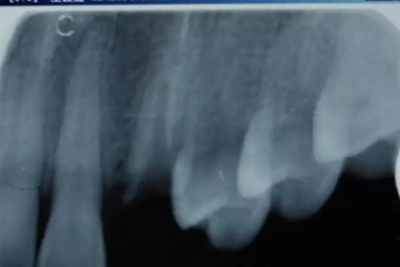

病例一 女性,20歲,大學(xué)生,要求補(bǔ)牙,檢查口內(nèi)可見A6大面積缺損,近中牙齦息肉,拍X片,根管充填物略差,但根周未見明顯陰影,口內(nèi)檢查無(wú)叩痛。建議患者冠延長(zhǎng)手術(shù)+高嵌體修復(fù)。

患牙遠(yuǎn)中邊緣嵴完整,強(qiáng)度沒(méi)有降低,故擬保留遠(yuǎn)中邊緣嵴,高嵌體修復(fù)。首先去除腐質(zhì)及原墊底材料,流體樹脂+3M Z350XT樹脂墊底。局麻下行冠延長(zhǎng)手術(shù)。在此需要提及個(gè)人的一個(gè)觀點(diǎn)。冠延長(zhǎng)手術(shù)原則上要求3-6個(gè)月以上才能永久修復(fù)。但是個(gè)人喜歡后牙肩臺(tái)建立在齦上,所以修復(fù)后的修復(fù)體邊緣位于牙齦上方1mm,對(duì)牙周的愈合影響較?。ㄈ绻麨辇l下邊緣則要慎重),故該患者術(shù)中按照齦上邊緣的設(shè)計(jì)進(jìn)行冠延長(zhǎng)手術(shù)。以下為術(shù)中: